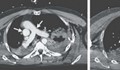

Мъж живя осем години с нож в гърдите си, без да разбере